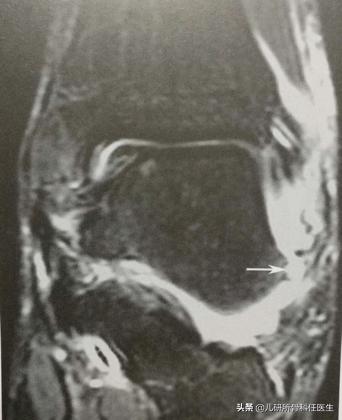

这种情况下,宝爸宝妈们往往能想到的就是拍摄踝关节X线片,但这往往只能排除是否有踝关节骨折。如果想近一步确定韧带损伤的情况,并知晓关节囊及关节软骨损伤的情况,踝关节的核磁共振更有必要。